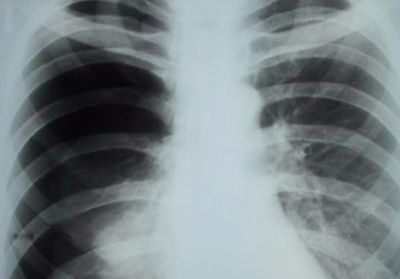

- Боль в спине справа бывает из-за пневмонии правосторонней. В этом случае ее интенсивность напрямую зависит от стадии болезни. Дополнительно всегда возникают присущие воспалению симптомы, которые и позволяют определить ее – это хрипы, температура и др.

Правостороннее воспаление легкого характеризуется тупой болью в правом боку, локализованной преимущественно в подреберье.

При длительном течении заболевания боль ощущается в груди и спине со стороны пораженного органа.